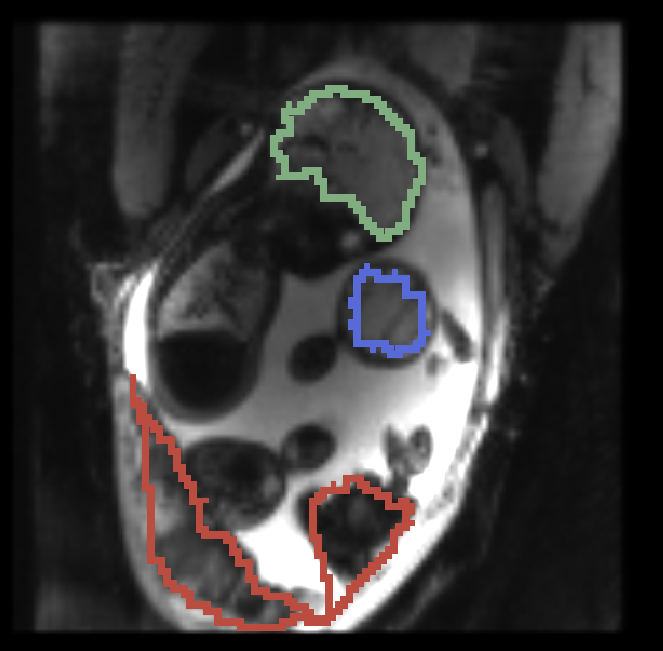

, manual segmentation on , manual segmentation on , propagated segmentation

, manual segmentation on , manual segmentation on , manual segmentation on

Fig. 3 provides example results from the study for fetal brains and placentae. We observe that the reference frame is warped accurately by the temporal registration algorithm in the regions of fetal brains and placentae to represent the first frame in the series that is substantially different from the template. The delineations achieved by transferring manual segmentation labels from the reference frame to the coordinate system of the selected frame are in good alignment with the manual segmentation outlines for that selected frame.